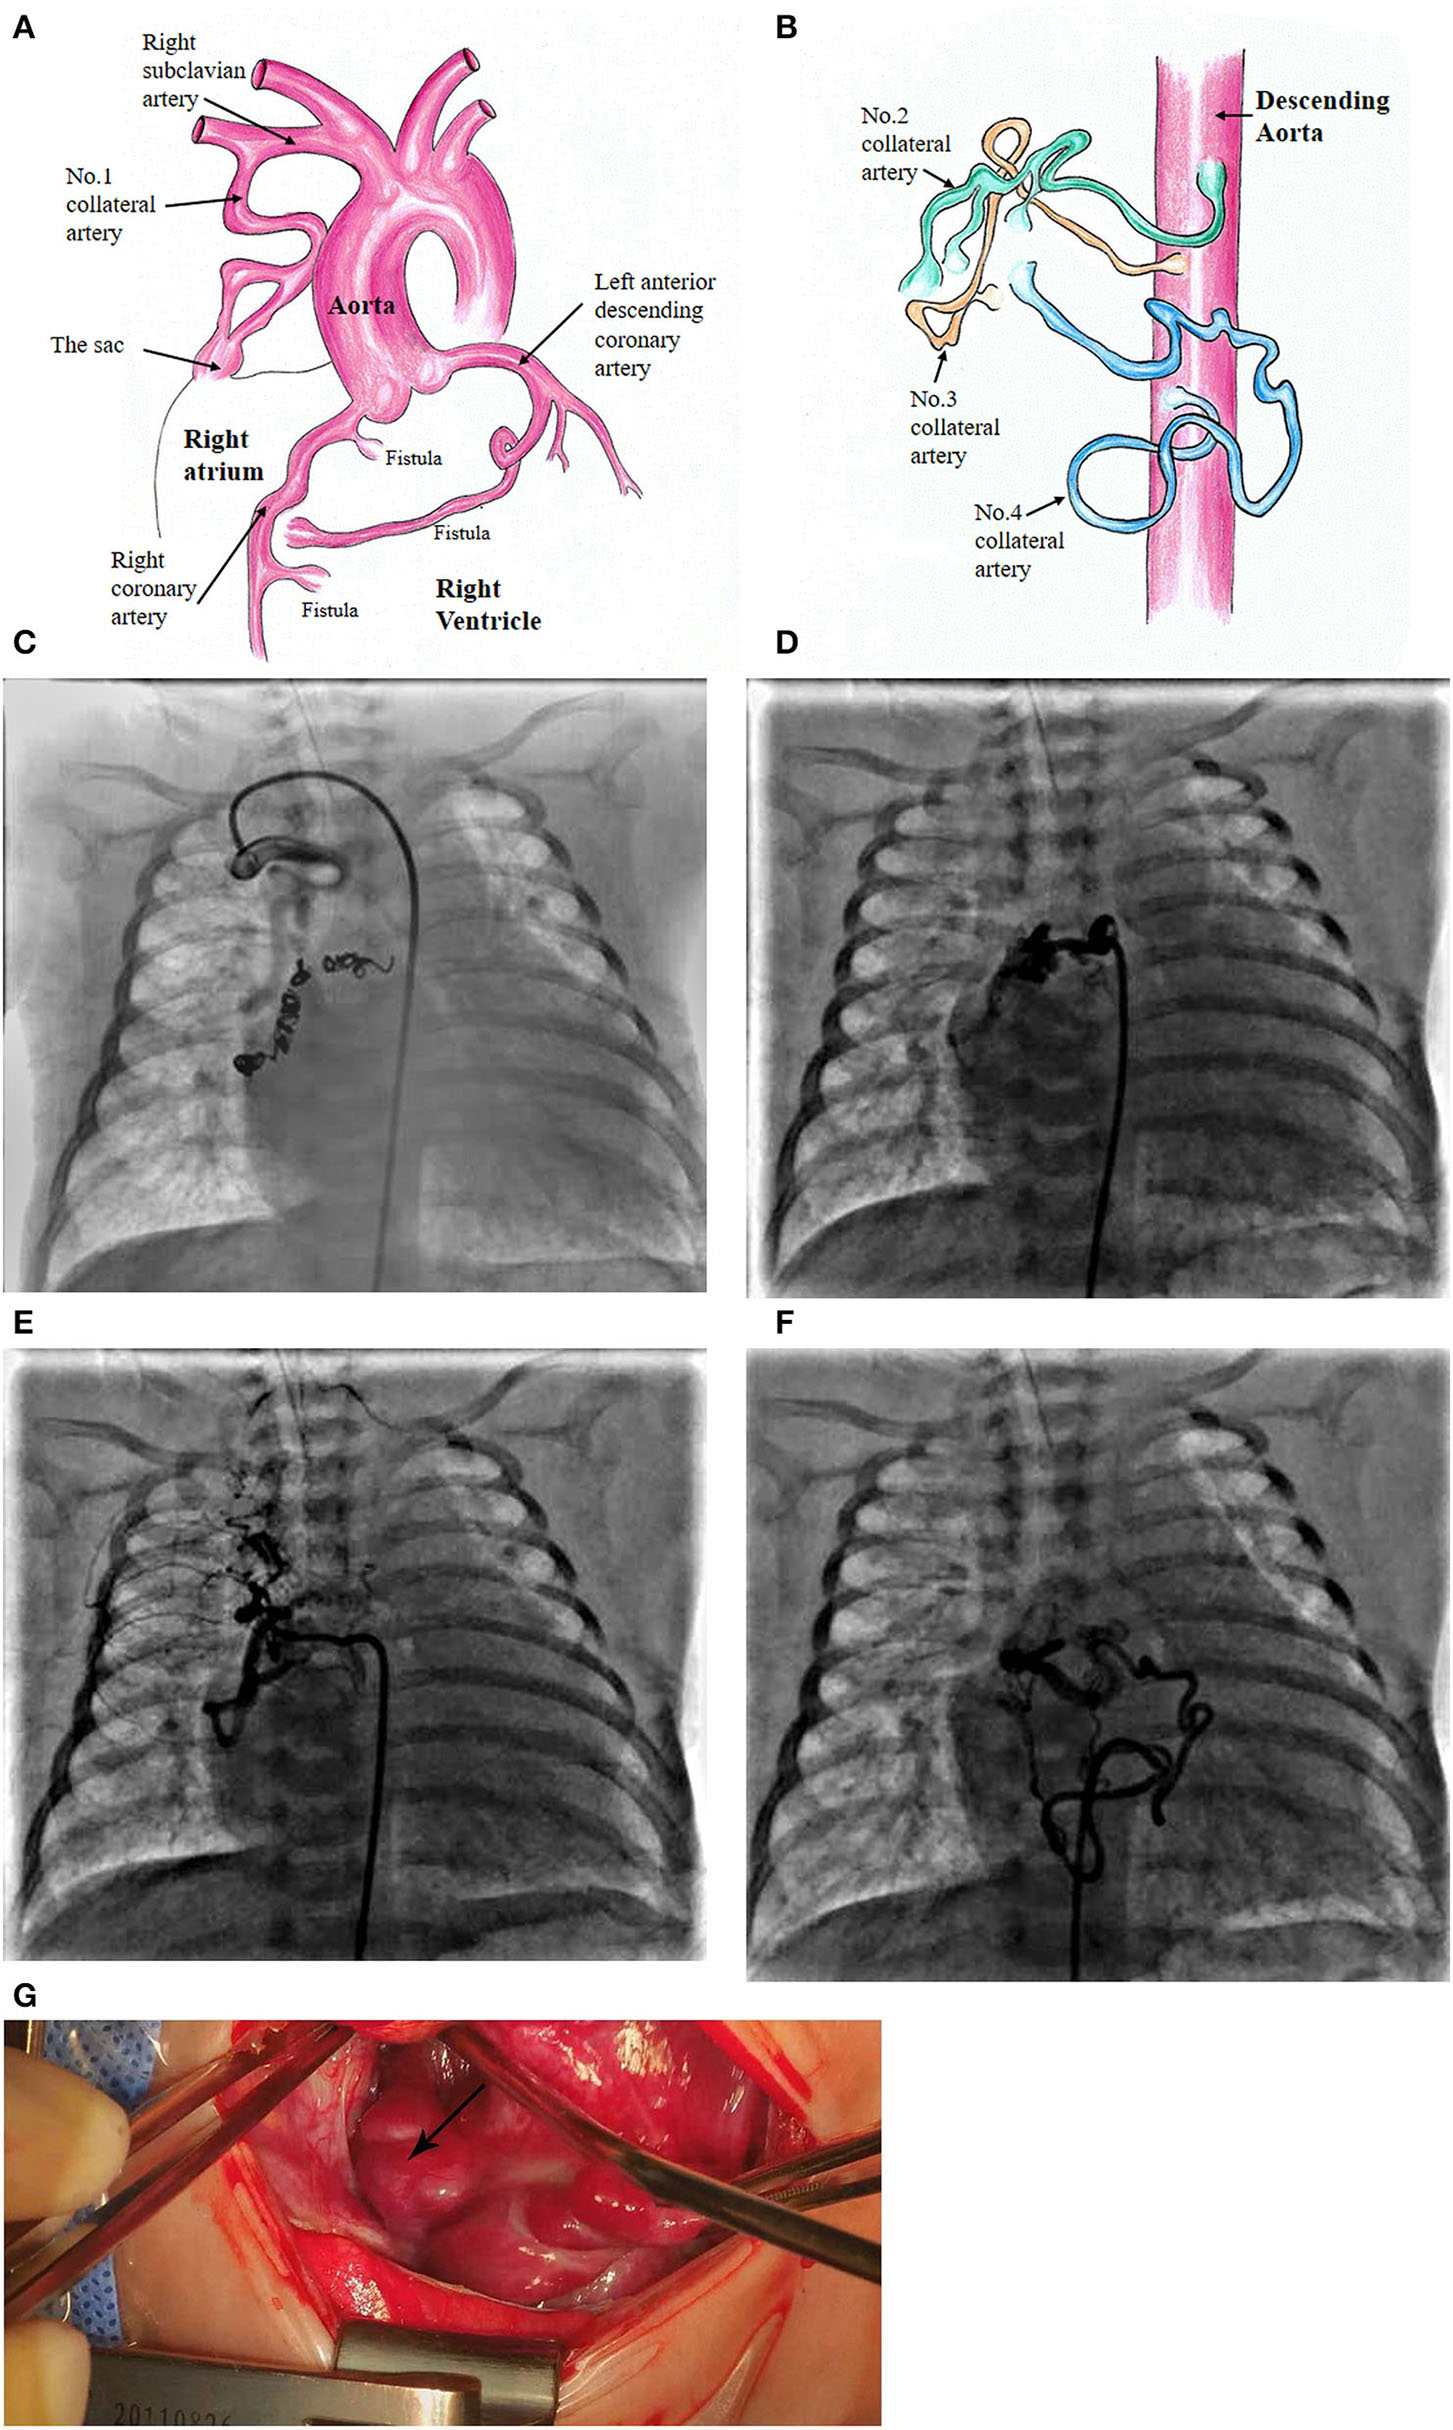

At the age of 5 weeks old, cardiac catheterization was performed for hemodynamic assessment and interventions. The pulmonary to systemic blood flow ratio was 4.29 with pulmonary vascular resistance 1.7 Wood unit *m2. A selective angiography revealed four collateral arteries draining into the right atrium. No. 1 (4.3 mm in diameter) of the collateral arteries was originating from the right subclavian artery (Figures 1A,C). No. 2 was seen at the level of the 6th thoracic vertebra and twisted to the right atrium (Figures 1B,D). No. 3 was a tortuous collateral artery (2.7 mm at the proximal and 1.7 mm at the minimal), located between the 6th and the 7th thoracic vertebra (Figures 1B,E). No. 4 was a very tortuous collateral artery between the descending aorta and the right atrium (Figures 1B,F). No. 1 and No. 3 collaterals were occluded with coils. Coronary arterial angiography also revealed a right coronary arterial fistula to the right ventricle and another to the right atrium (Figures 1A, 2A), and a fistula branching from the left anterior descending coronary artery to the right atrium (Figures 1A, 2B). Pulmonary arterial pressure was 43/22 mmHg.

Figure 1

Schematic diagram of the patient's diagnosis of 3 coronary artery fistulas to the right atrium and right ventricle, respectively (A). Four collateral arteries draining through a sac to the top of the right atrium (A,B). Super-selective angiogram shows the following collaterals terminating to the sac and then to the right atrium. No. 1 collateral artery originating from the right subclavian artery (C). No. 2 at the level of the 6th thoracic vertebra (D). No. 3 originating from the descending aorta (E). No. 4 located at the lower edge of the 9th thoracic vertebra (F). Surgical image of the sac at the top of the right atrium (G).

More details were found at cardiac surgery at the age of 6 weeks old. A 15-mm sac was found an opening to the top of the right atrium (Figures 1A,G). Three collateral arteries originated from the anterior and posterior walls of the descending aorta and another from the right subclavian artery coursed into the sac and then the right atrium. The patent ductus arteriosus (4 mm) was ligated and cut down. Subsequently, a cardiopulmonary bypass was performed to suture the openings of the sac and the coronary arterial fistulas. The remaining two collateral arteries were clipped.